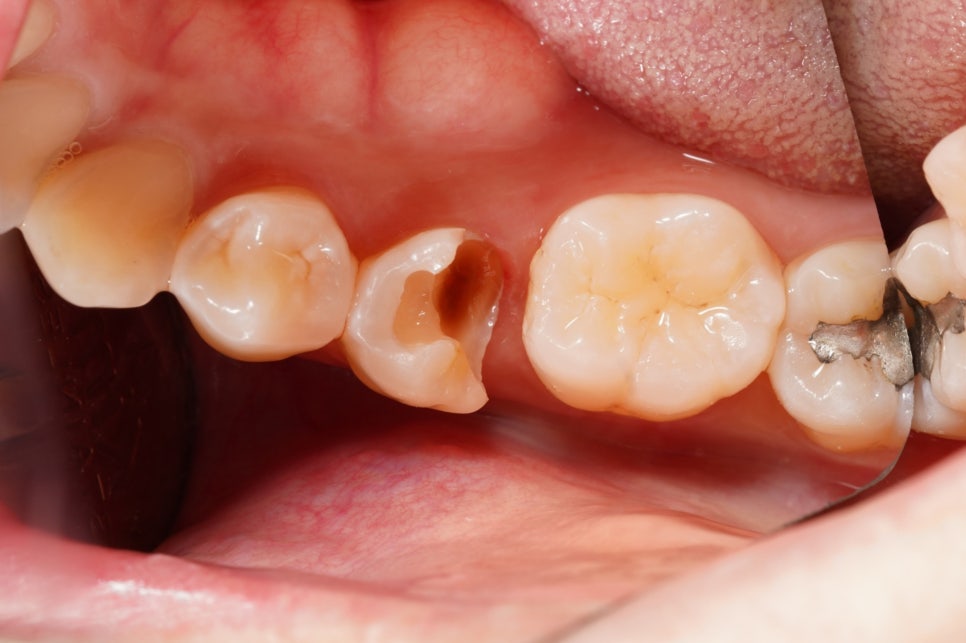

웬만한 치과에서는

'신경치료' 진단을 내렸을 법한

다양한 케이스들도 사실은

(물론 100%는 아니지만)

접착 치의학에 기반한

최소침습 치의학,

<레진 빌드업>으로

당일에 끝낼 수도 있습니다.

분명히 신경치료가 필요한,

심지어는 발치가 필요한

충치 치아들이 있습니다.

그런 치아들까지

모두 레진으로 할 수 있는 것은

절대로 아니겠죠.